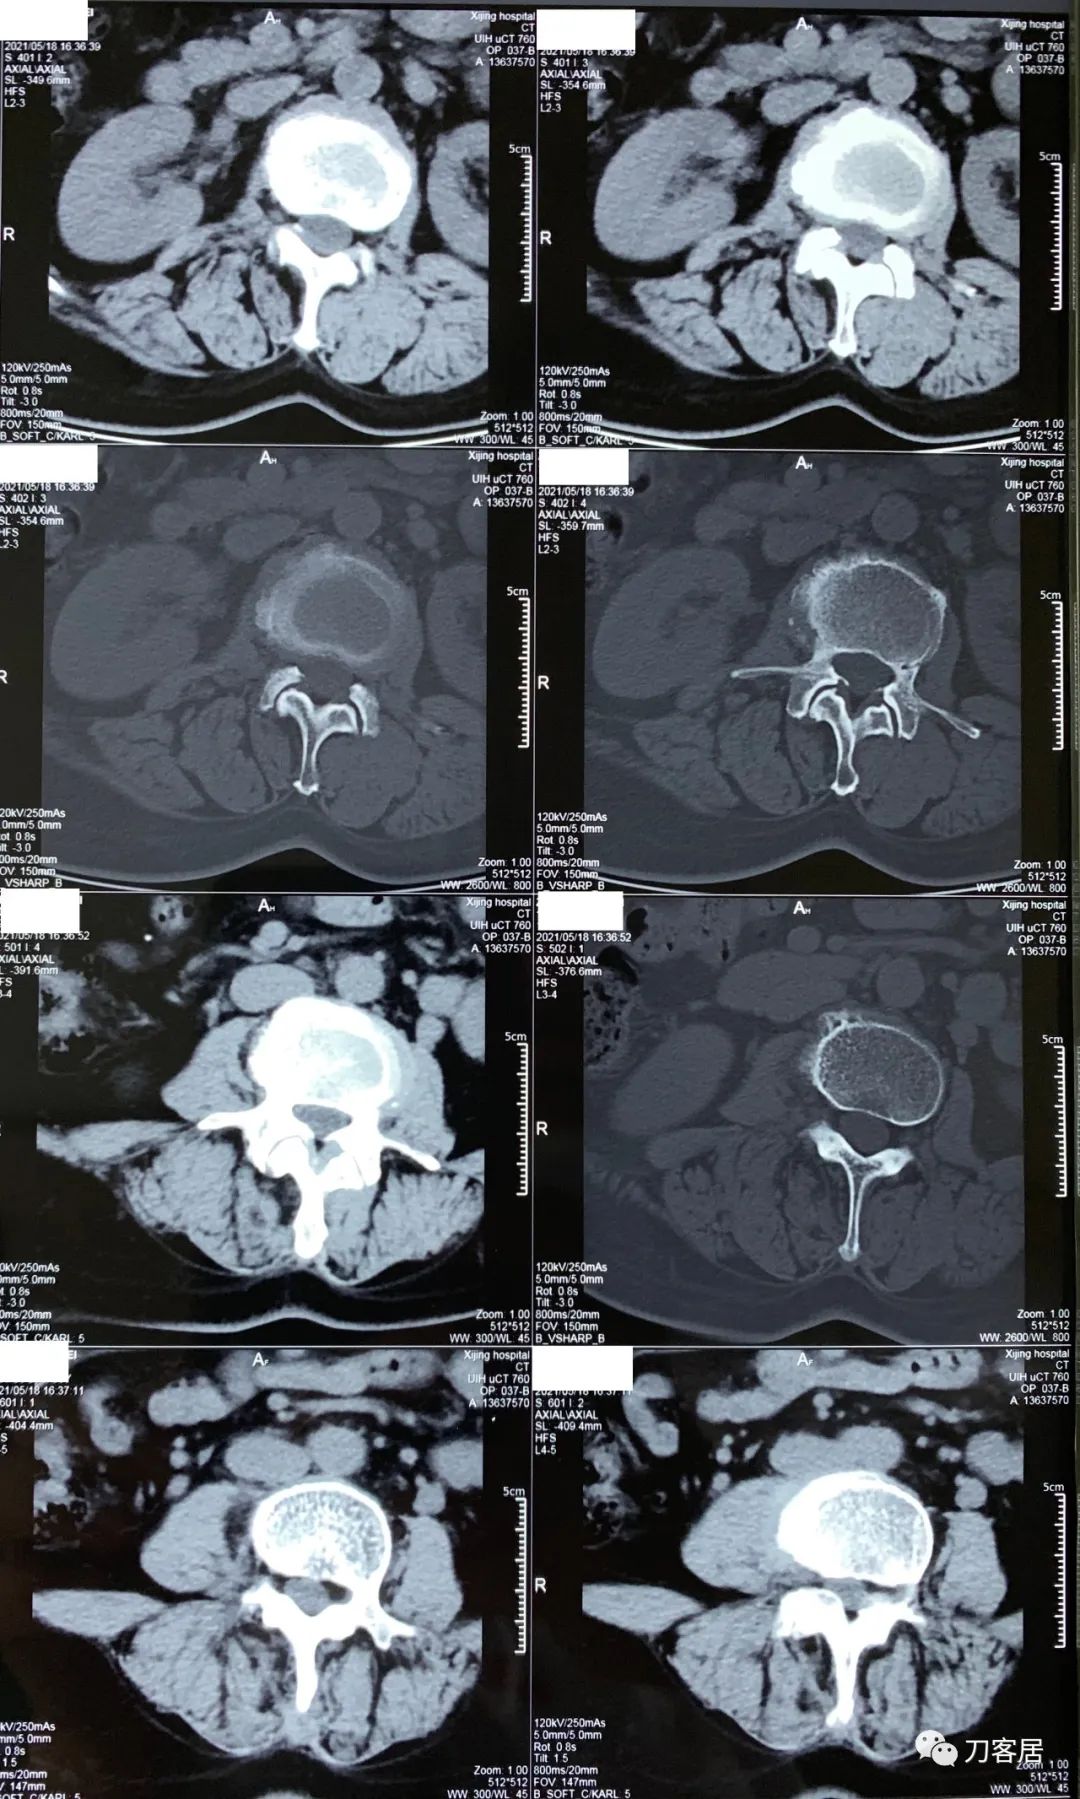

2021年5月17日,西京医院骨科门诊找我就诊,自带影像学检查资料提示腰椎侧弯,腰3-4,腰4-5椎间盘突出,黄韧带肥厚,椎管狭窄。

建议其查双光子骨密度,骨盆正位片以及腰椎间盘平扫。腰椎正侧位X线片以及动力位片,站立位脊柱全长正侧位X线片,以了解其是否有骨质疏松,并了解脊柱侧弯情况,腰椎局部X线表现情况和腰椎间盘突出和椎管狭窄情况。

从这个患者的影像资料分析,颈椎间盘突出问题不大,没有明确的上位神经元损伤表现,所以,不考虑颈椎和胸椎问题。腰椎侧弯畸形,但不严重。因为存在腰椎侧弯,使得腰椎MRI在扫描切面的时候,显示的椎间盘突出或椎管狭窄会有一定的误差,所以,又加做了经椎间盘的CT平扫,影像表现并不严重,综上,腰椎间盘突出,腰椎管狭窄,腰椎侧弯,不考虑手术治疗。同时,患者的主要痛苦是心理疾病,而不是器质性疾病,所以,以心身疾病治疗为主。虽然患者骨密度检查结果提示正常,但X线片显示骨质疏松,且其症状也与骨质疏松的症状有符合之处,比如静息痛,不能入睡,动作及姿势变换时痛加重等,所以,给予实验性抗骨质疏松治疗,以观疗效。